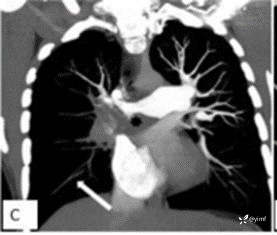

既往史:患者5年前因坐火车长达12个小时,腿部血液流通不畅进而形成下肢深静脉血栓(DVT),此后规律口服了6个月的利伐沙班进行抗凝治疗。此后没有进一步调查血栓形成原因,因无不适症状未服任何抗凝药物。4年前患者因呼吸困难,行相关检查示肺栓塞(相关影像学资料见图1A-C),并进行了紧急溶栓治疗。在此之后,他接受了利伐沙班治疗,并继续服用至今。

图1 CT肺动脉造影(CTPA)

图2 CT肺动脉造影显示右肺动脉有残余慢性血栓,主肺动脉扩张